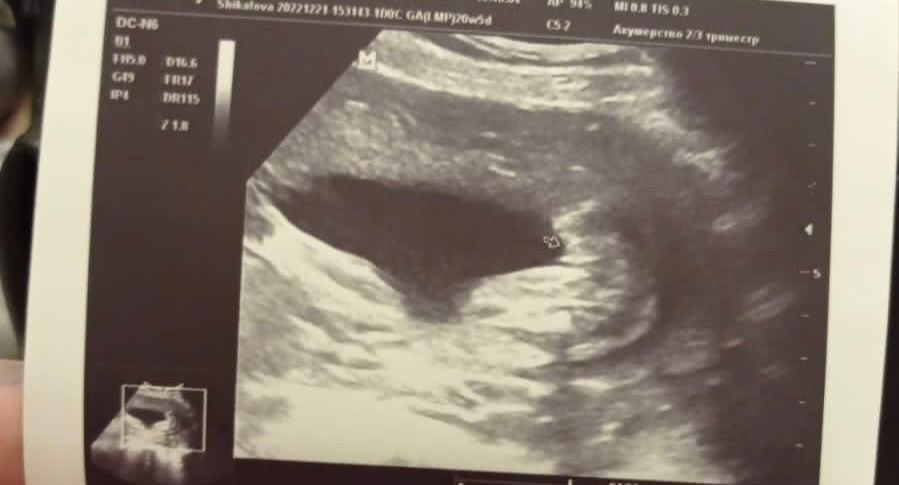

Помогите определить по узи девочка или мальчик ? Или не понятно ?

Четко зернышко кофейное у вас❤️девчушка

Похоже на девочку

Врачу виднее конечно, но на снимке ничего от мальчика нет.

Девочка. Ничего мальчикового нет)) На Вашем сроке, тем более, ошибка маловероятна.